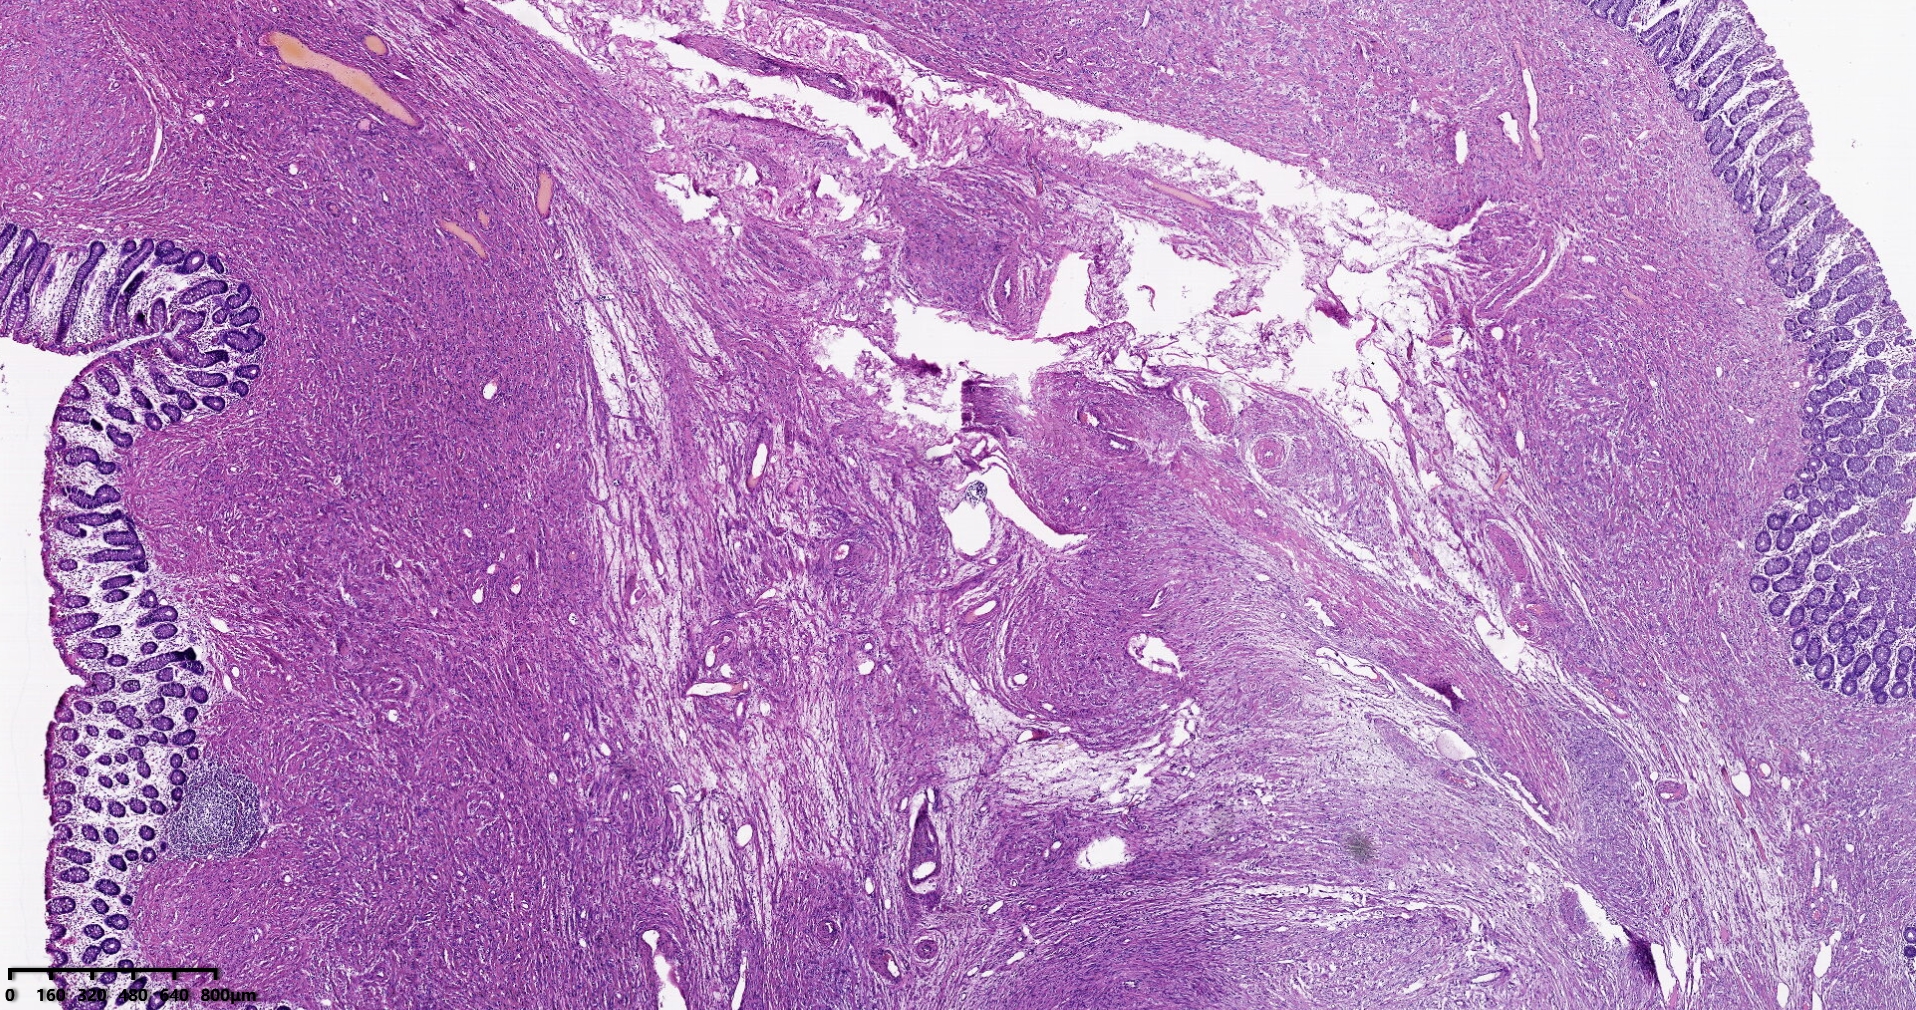

结肠肝曲息肉状肿物,平滑肌瘤?胃肠道间质瘤?炎性纤维性息肉?

性别

男

年龄

56岁

临床诊断

结肠肝曲息肉

一般病史

不详

标本名称

大体所见

灰红色椭圆形息肉一个,直径2.5cm,蒂长0.5cm,切面灰白灰红色,质中。

请路过的老师指教。

图1

考虑间质瘤?

就HE形态而言,间质瘤的可能性要大一些,建议做免疫组化协助鉴别。